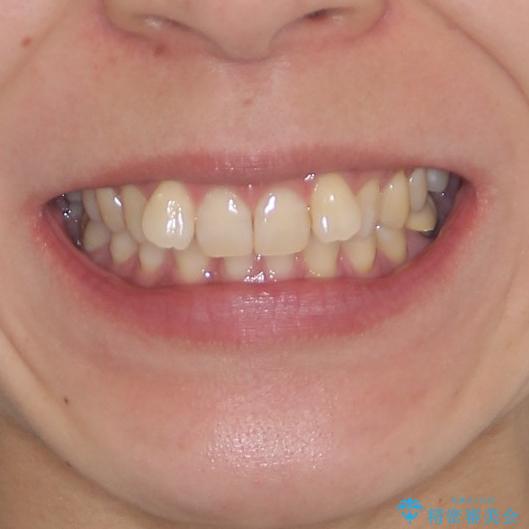

下顎2前歯の欠損 インビザラインによる抜歯矯正

- 下顎前歯欠損による歯列不正を気にして来院された患者様です。

マウスピースでの抜歯矯正特有の抜歯スペースに向かって奥歯が傾斜する動きが顕著に表れ、ディープバイトは改善されませんでした。